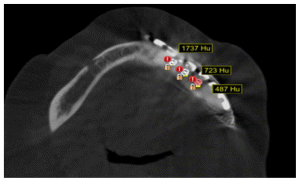

The patient after surgery continued under observation and could not continue with her treatment due to the Covid epidemic, resuming the treatment on 03/02/2014 for the reassessment by CT the new bone formed in the area of surgery was observed by two programs Blues Sky Bio and Mimics of Materialise the values in Hounsfield units were determined in each of the CT slices at the sites planned for the placement of three implants, the values ranged from 209 U. Hounsfield to 1372 U. Hounsfield (Figs, 15,16,17,18).

In the CT scan, the bone regeneration of the morphogenetic protein BMP2 (Cowell PLUS BMP) and the growth factors with the Chucron technique were verified, managing to observe a good bone conformation, however, a bone formation was observed towards the upper part of the jaw that did not follow any anatomical pattern of the mandibular body and was attached to the mandibular body. (Figures 19,20, 21)